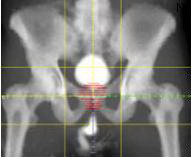

xa_phau_5.jpgNăng lượng photon dùng dể điều trị khối u ở độ nông sâu khác nhau như u vùng tai mũi họng, vùng cổ, u phổi, u trung thất, các khối u vùng bụng và tiết niệu, khối u xương, não, đầu, cổ, ngực, phổi, hạch bạch huyết, tuyến tụy, xương chậu và các bệnh ở trẻ em..

Với những ưu điểm này, máy Primus có thể điều trị hiệu quả khối u ở mọi vị trí: trong não, đầu mặt cổ, phổi, các tạng trong ổ bụng, hạch bạch huyết...